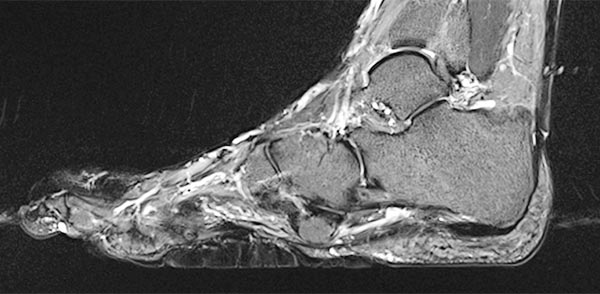

Präoperative Abklärung des Bindegewebsnävus in der MRT, hier sagittale T2-gewichtete, fettunterdrückte Sequenz des rechten Fußes. Der Bindegewebsnävus ist aufgrund des hohen fibrotischen Anteils homogen hypointens (schwarz).

Auch in der nativen, T1-gewichteten MRT sagittal ohne Kontrastmittel (gleiche Schnittebene) ist der Bindegewebsnävus homogen hypointens (schwarz).

In der sagittalen , T1-gewichteten, fettunterdrückten MRT (wieder gleiche Schichtebene) findet sich ein geringes, relativ homogenes Enhancement des Nävus.